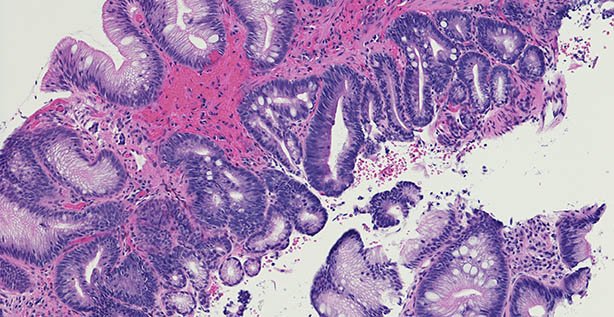

Oesophageal adenocarcinoma is the sixth-most common cause of cancer death worldwide (five-year survival is less than 10 per cent), and is on the rise, with Barrett’s oesophagus the biggest risk factor.

As aspirin reduces inflammation and PPIs reduce acid reflux, the Aspirin and Esomeprazole Chemoprevention in Barrett’s metaplasia Trial (AspECT) aimed to evaluate the efficacy of high-dose esomeprazole PPI and aspirin for improving outcomes in patients with Barrett’s oesophagus, explained lead author Prof Janusz Jankowski, Senior Consultant Physician, University Hospitals Morecambe Bay, UK.